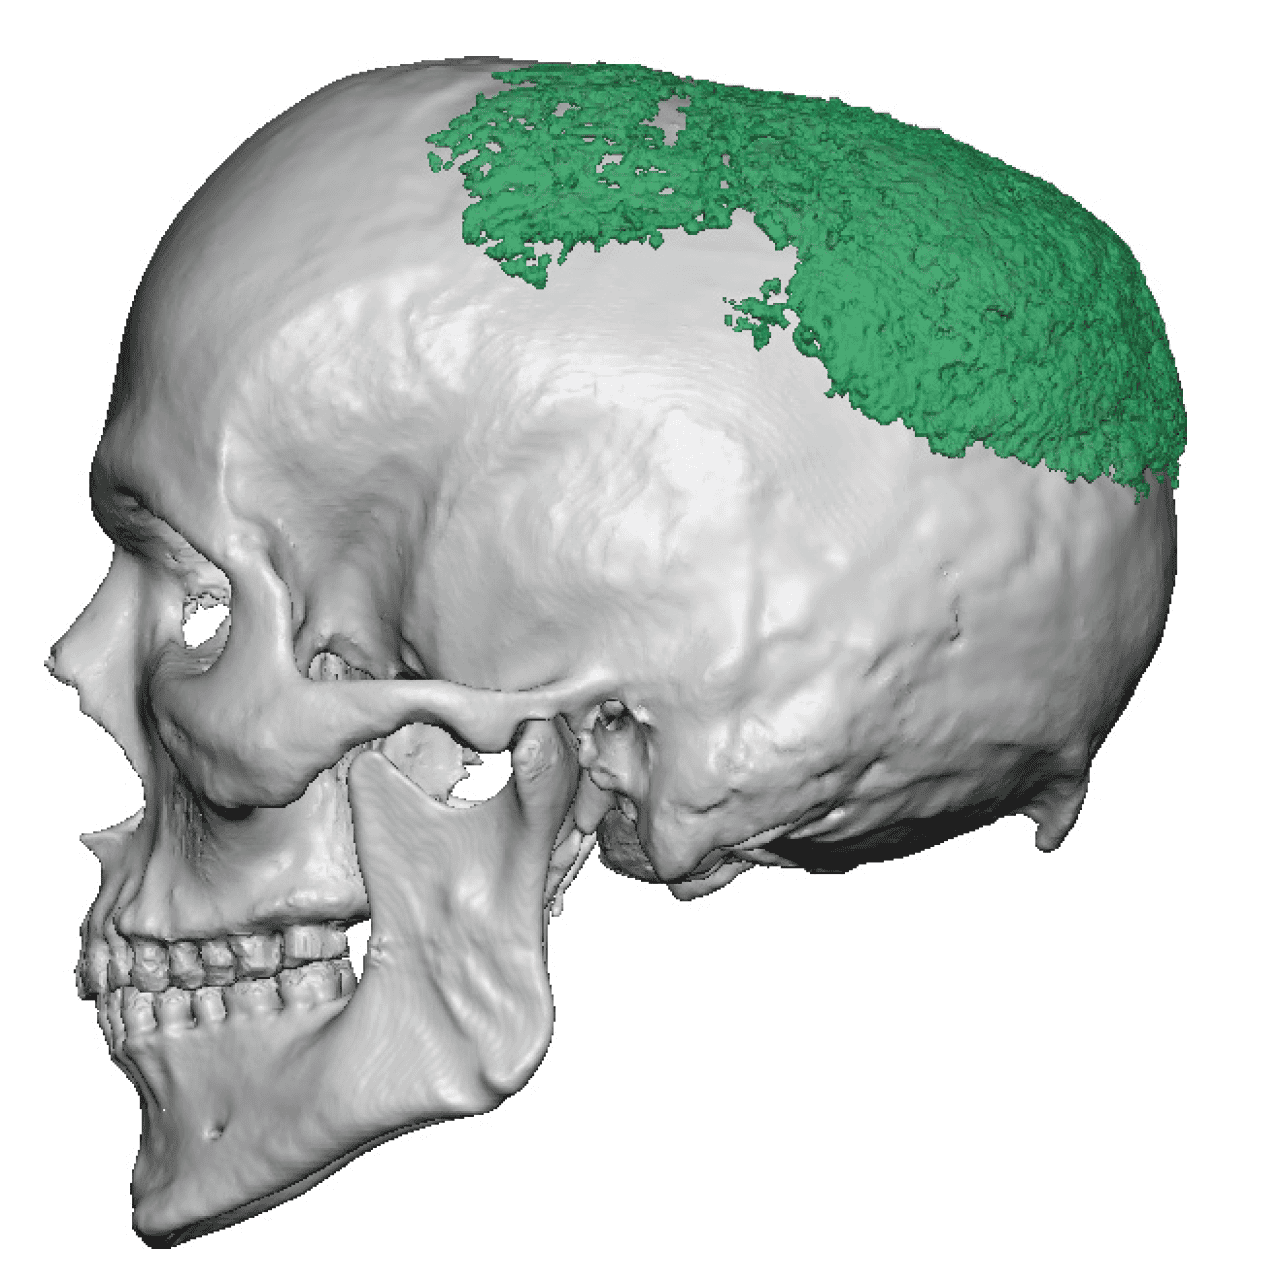

Desire for change of head shape from front view form an inverted V shape to a rounder and wider head shape.

Placement of custom extended forehead-temporal implants through incisions in the crease behind the ear. (he had a prior back of head skull implant which is green in the implant designs and which the head widening implants partially covered it)